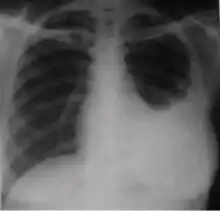

4. Pleural effusion - Presence of a significant amount of fluid within the pleural space. This finding must be distinguished from blunting of the costophrenic angle, which may or may not represent a small amount of fluid within the pleural space (except in children when even minor blunting must be considered a finding that can suggest active TB).

Chest x-ray of pleural thickening post-primary tuberculosis

1. Pleural thickening - Irregularity or abnormal prominence of the pleural margin, including apical capping (thickening of the pleura in the apical region). Pleural thickening can be calcified.

3. Blunting of costophrenic angle (in adults)—Loss of sharpness of one or both costophrenic angles. Blunting can be related to a small amount of fluid in the pleural space or to pleural thickening and, by itself, is a non-specific finding (except in children, when even minor blunting may suggest active TB). In contrast a large pleural effusion, or the presence of a significant amount of fluid in the pleural space, may be a sign of active TB at any age.